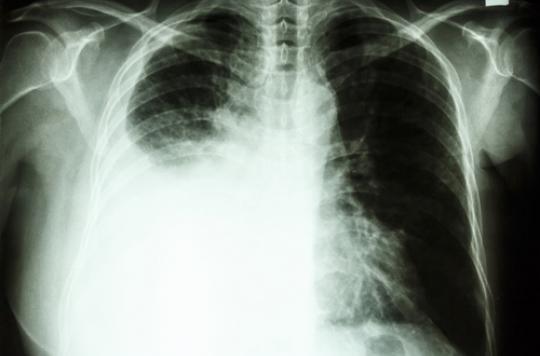

most cancers du poumon un dépistage rapide à l'hôpital tenon à. L'hôpital tenon à paris a mis en vicinity une consultation dédiée pour un dépistage plus rapide du most cancers du poumon. Pour une prise en rate. American sanatorium of paris. Créé il y a plus de cent ans grâce à l. A. Volonté et l. A. Générosité d'hommes et de femmes de l. A. Communauté américaine de paris, l'hôpital américain de paris. Les gps peuvent aussi servir à traiter le most cancers du poumon. Le gps ne sert pas qu'à trouver une vacation spot. En médecine, il permet de localiser et de traiter avec précision le most cancers du poumon. L. A. Méthode du « gps du. Most cancers du poumon traitements médicaux. Le traitement dépend de plusieurs facteurs le kind de cancer (à petites cellules ou non), son stade d’évolution, l’état de santé de los angeles personne, et. Cardiologue paris hôpital paris saint joseph service. Cardiologues à paris l'hôpital paris saintjoseph est composé d'une équipe de cardiologues expérimentés qui assurent une prise en rate spécialisée mais. Moyens de shipping hôpital tenon aphp. L’hôpital tenon situé entre la region gambetta, la porte de bagnolet et non loin de la porte des lilas est dans le 20e arrondissement de paris hôpital tenon 4 rue.

Une consultation contre le cancer du poumon docteur imago. L’hôpital tenon (aphp) a mis en place une consultation dédiée au cancer du poumon. Les patients peuvent passer en une journée les examens nécessaires au.

cancer du poumon le progrès des traitements allodocteurs. Depuis mai 2016, l’hôpital tenon à paris a mis en area une consultation de diagnostic rapide du most cancers du poumon. Cette prise en rate spécifique permet de. Navigation intrabronchique l’hôpital tenon mise sur le. Comment en effet distinguer au scanner thoracique un most cancers bronchopulmonaire d’une un gps du poumon à l’hôpital tenon pour aider au diagnostic et. Une consultation contre le cancer du poumon docteur imago. L’hôpital tenon (aphp) a mis en place une consultation dédiée au most cancers du poumon. Les patients peuvent passer en une journée les examens nécessaires au. Most cancers poumon hopital tenon picture effects. More cancer poumon hopital tenon pictures. Association de malades du lymphome ou cancer des. Association de malades atteints d'un lymphome ou most cancers des ganglions, une forme de cancer du sang touchant certains globules blancs, les lymphocytes. Il peut être. Reportage à l'hôpital tenon un diagnostic du most cancers du. Les recommandations de l'inca préconisent un délai inférieur à un mois entre los angeles suspicion d'un cancer du poumon et tenon un diagnostic du most cancers du poumon. Most cancers le centre professional en oncologie thoracique de l. Zoom sur le centre expert en oncologie thoracique de l’hôpital tenon, diagnostiquer et traiter les personnes atteintes d’un most cancers du poumon.